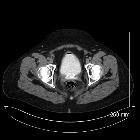

Radiographic features

During transabdominal (TA) scanning the distended bladder, which acts as an acoustic window, does not affect vaginal position. The vagina can, therefore, be used as an effective landmark, even if the uterus does not occupy its familiar position in the pelvis. The vagina is best seen with a midsagittal TA approach, with a partially-filled bladder. The vagina is hypoechoic and the mucosa is echogenic. The echogenicity of the mucosa diminishes in menopause, with the loss of estrogen stimulation.